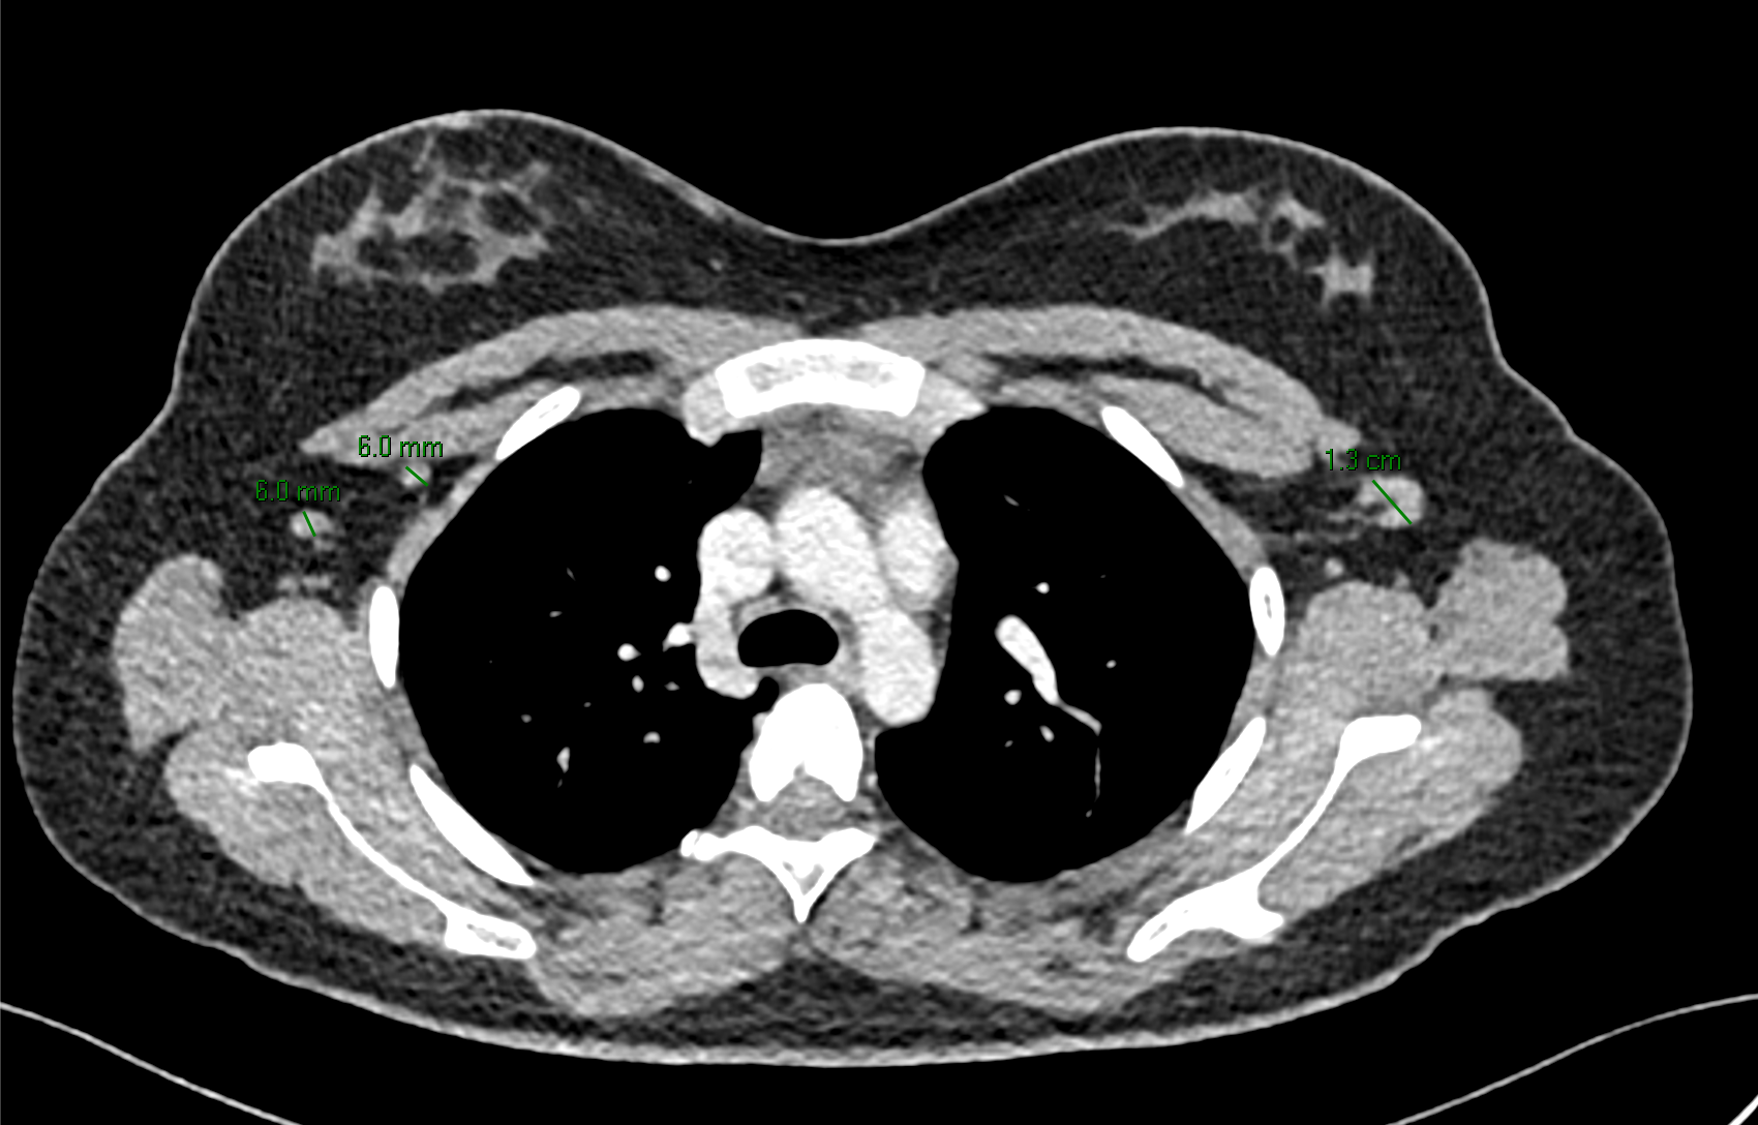

Imágenes de tomografía en adquisición axial en ventana para tejido blando, fase venosa, con su correspondiente correlación con imágenes de PET CT.

K. Región axila derecha con presencia de múltiples ganglios de morfología ovoidea, con pérdida de su hilio graso central y eje corto de hasta 6 mm. Región axilar izquierda con ganglio que conserva morfología, hilio graso con eje corto de hasta 13 mm.

I. Imagen de PET CT con adenopatías axilares bilaterales asociadas con hipermetabolismo.